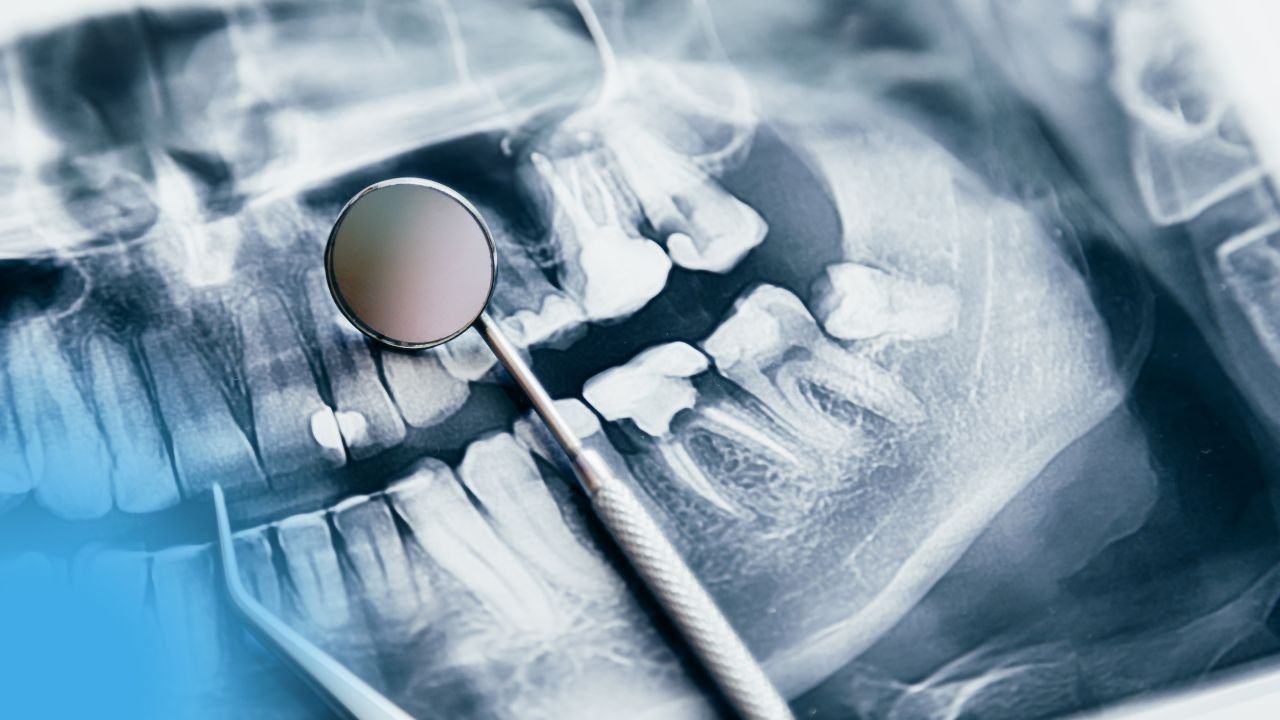

LESIONS CARIEUSES (Radiologie)

LESIONS CARIEUSES (Radiologie) I. DÉFINITION La lésion carieuse est un symptôme, visible ou non, cliniquement et/ou radiologiquement.Le processus carieux invisible...